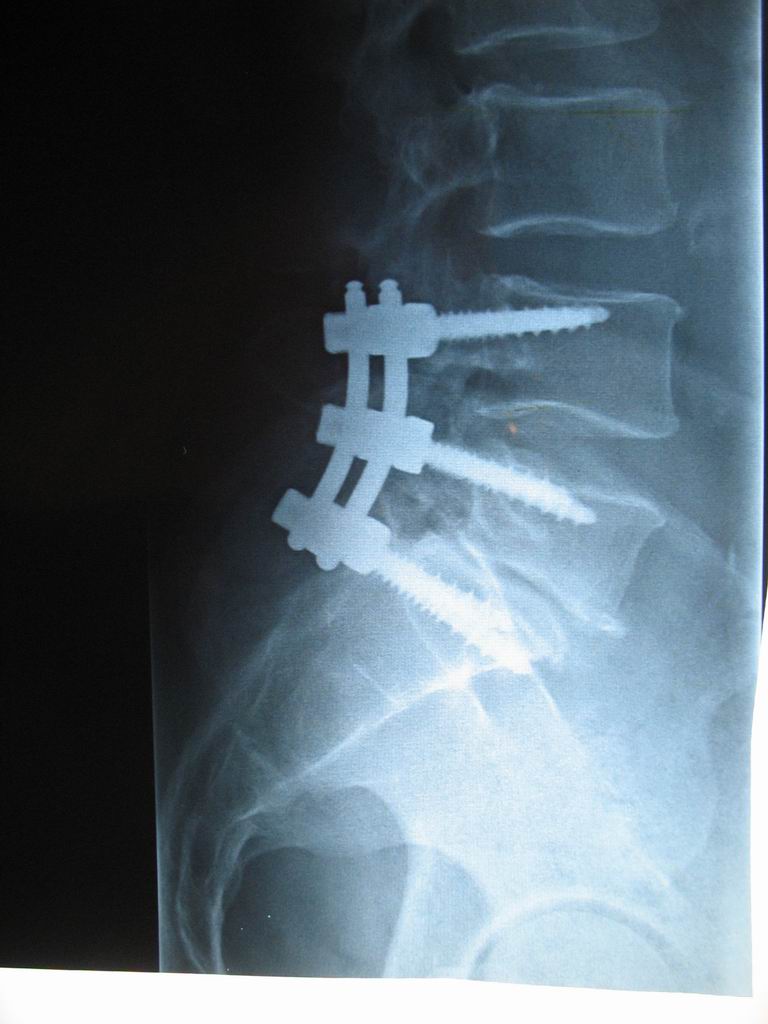

I had major back surgery in April 2013, click here for details

Update April 2013. I had major back surgery on the 9th and my major worry was getting a chest infection so I made up my own saline and took it with me. I was put under the care of respiratory physician Dr Simon Bowler and he was surprised that I was using such a strong saline mix. He said that he recommends to all of his Bronch patients to use 7% saline every day.

Here is a photo of my new screws installed in my spine: